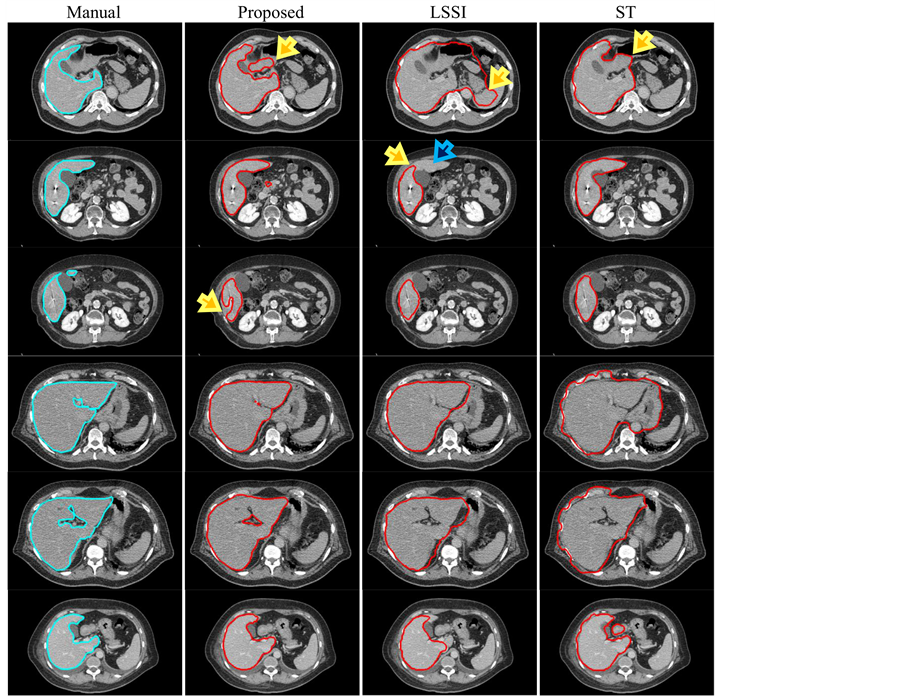

In Figure 8, an accumulated error from previous images and an overlap of gray-intensities between liver and another soft tissue caused some over-segmentations in all methods as shown in the first row. Liver segmentation based on the LSSI technique met a problem of the curve propagation in thin regions (see a yellow arrow in the second row). The given curve was unable to move into the remaining part of the liver’s region as indicated by a blue arrow. From observation, this problem occurred after a liver’s region in a given image was separated into two parts by edges in a speed image of the LSSI technique, and an initial region of the zero LSF was created inside the only one part. When we compared our proposed method with the LSSI and ST techniques, the proposed method achieved the best fitting boundaries of liver’s regions. These comparisons are illustrated in the remaining rows. However, these results did not clearly display hole-regions as shown in the outlines of manual delineation.

Figure 8. Six examples of liver-segmentation results in axial-images of patient A (phase 0 slice 66), B (phase 20 slices 73 and 83), C (phase 0 slices 94 and 100), D (phase 50 slice 50), which are presented from top to bottom.